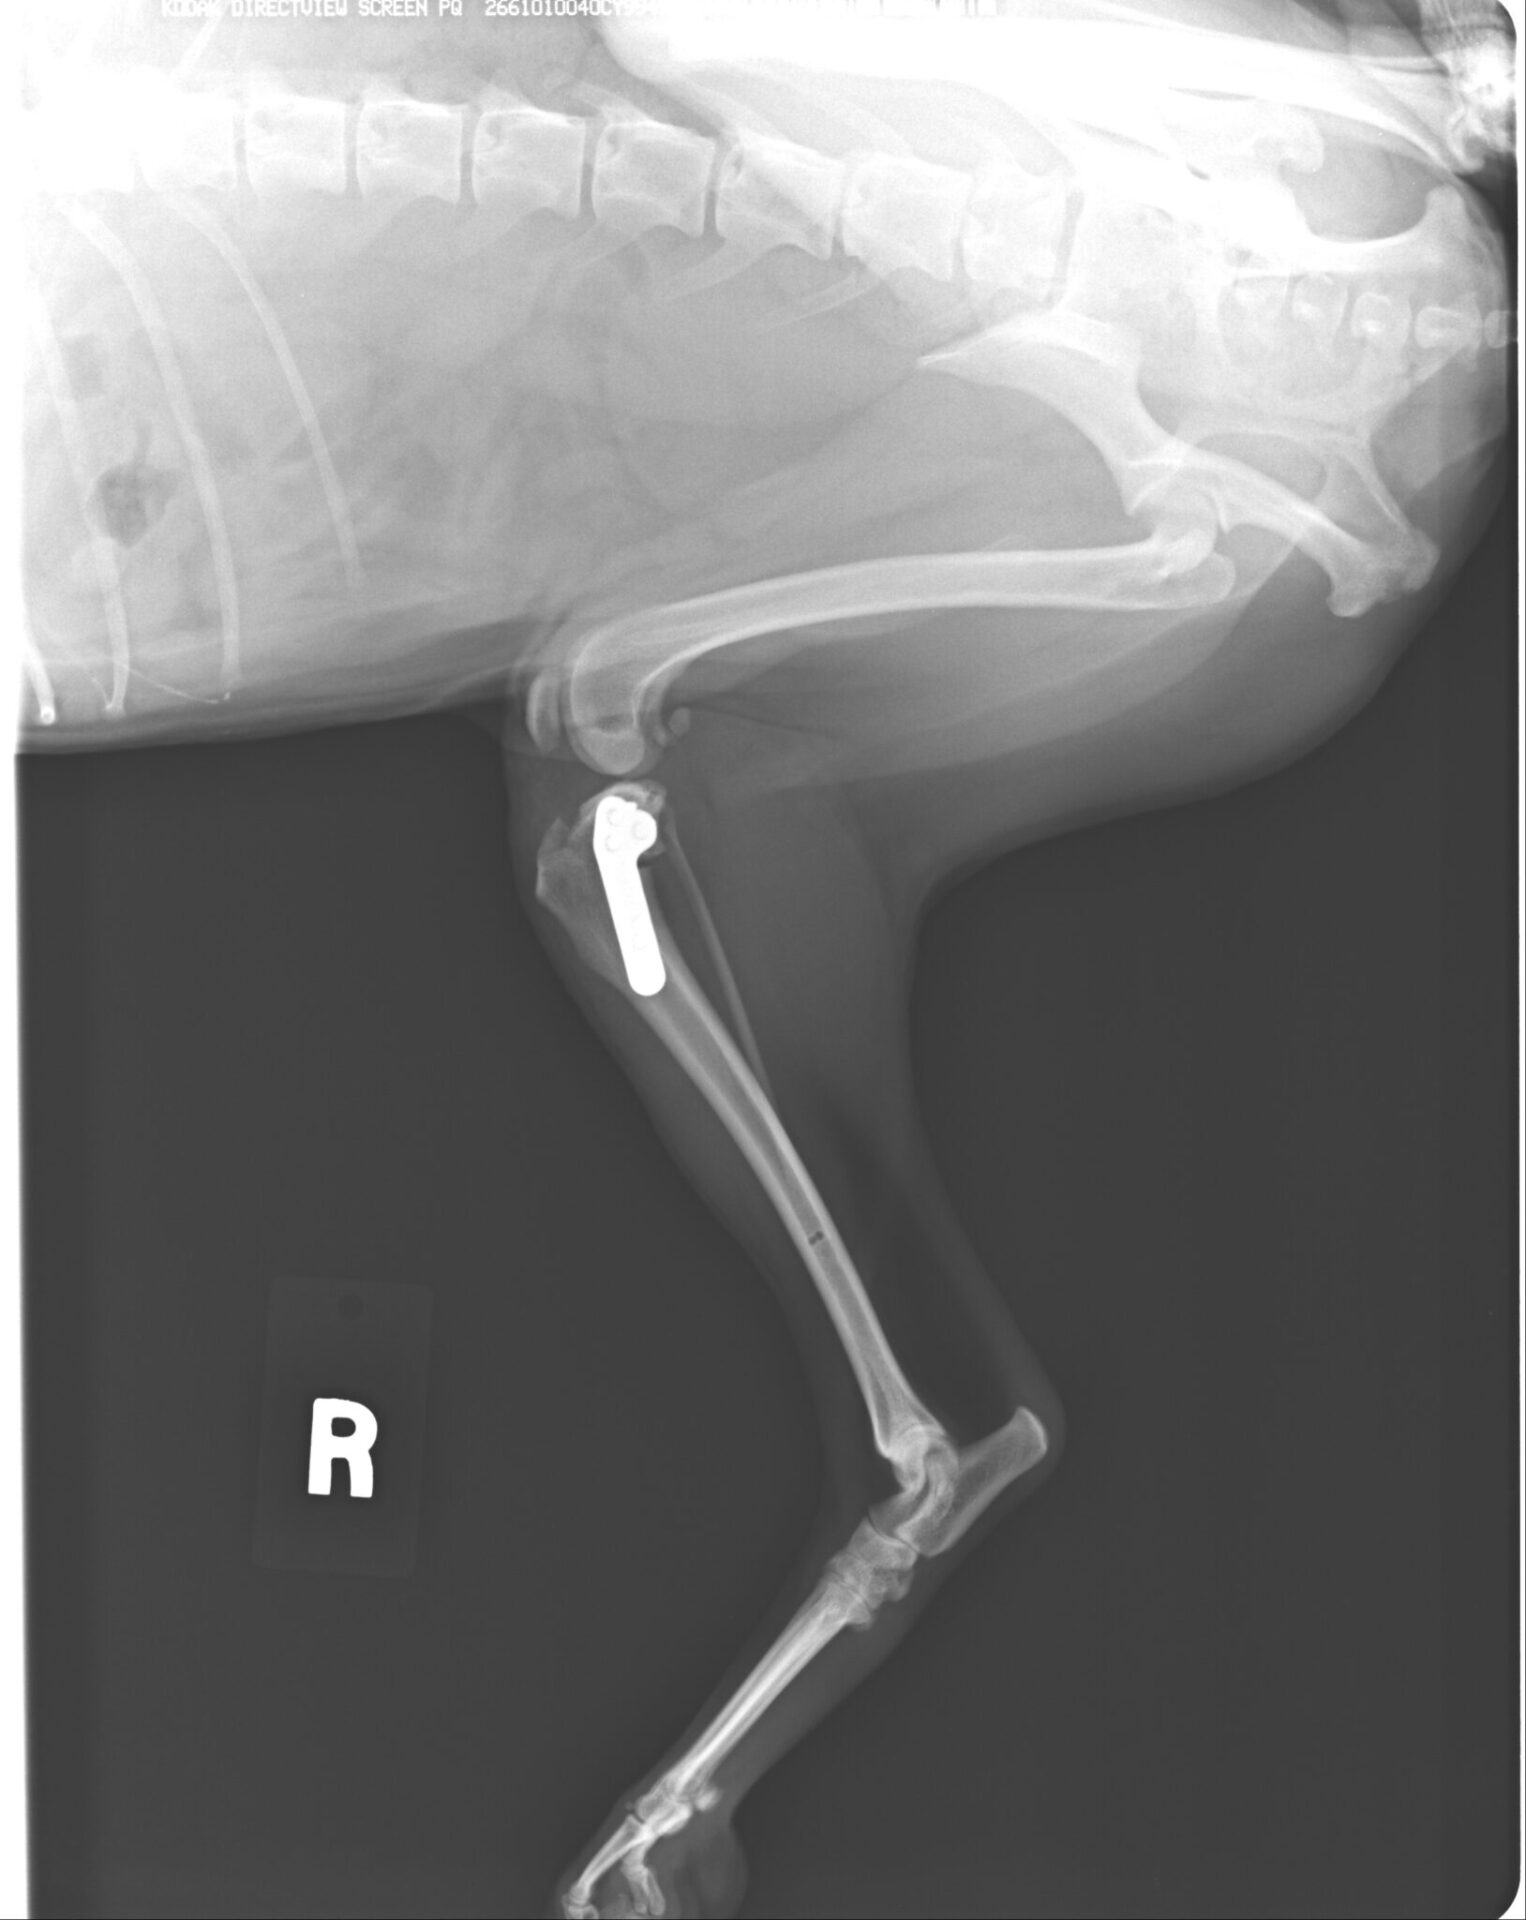

骨端部骨幹端骨折(術後)

ダブルプレートによる強固な内固定ではピンニングと比べると、早期に歩行が可能になります